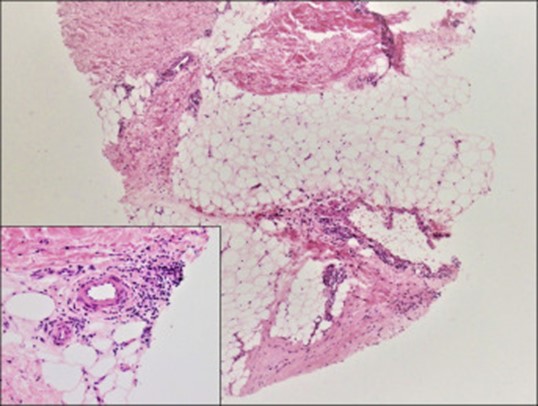

Image of biopsy of eosinophilic fasciitis

Image from reference 15.

A biopsy of the fascia has long been considered the gold standard for diagnosing EF. Histological findings include thickened, hyalinized fascial layers, with a lymphoplasmacytic infiltrate with or without eosinophils. (5) In the WSG, most patients (76.3%, 248/325) underwent MRI. Findings included thickening of superficial muscle fascia (40.7%, 101/248), thickening of deep muscle fascia (35.4%, 88/248), and edema (24.5%, 61/248). High-intensity signals were observed in the muscle fascia region for 76.6% (190/248) of patients. Twelve (4.8%, 12/248) had no abnormal findings. Fewer patients (16.3%, 53/325) underwent ultrasound. Findings included thickening of the skeletal muscle surrounding the region of induration (13.2%, 7/53), thickening of the superficial/deep fascia (24.5%, 13/53), and thickening of subcutaneous tissue (7.54%, 4/53). Seven (13.2%, 7/53) had no abnormalities and three (5.67% 3/53) had post-resolution imaging done at follow-up appointments. The authors recommend “that tissue biopsy, the gold standard, be performed in all suspected EF cases. MRI may be clinically useful as an adjunct to biopsy when biopsy is negative but a strong clinical suspicion for EF remains. Ultrasound should be used as a cost-effective method to assess posttreatment resolution of EF and long-term reemission.” (11) Shahriari et al evaluated 68 EF patients. Sixty percent (n = 41) of patients underwent a full-thickness wedge biopsy, 68% (n = 46) underwent MRI, and 34% (n = 23) underwent both wedge biopsy and MRI. In this cohort, wedge biopsy had a sensitivity of 95.1% in detecting fascial changes consistent with EF, while MRI had a sensitivity of 93.5% (P value = .99). This demonstrates that there was no statistically significant difference between these 2 modalities in diagnosing EF. The authors concluded: “Given these results and the potential complications from a wedge biopsy in a patient with cutaneous sclerosis, MRI may be considered as an appropriate modality to diagnose EF in lieu of a wedge biopsy.” (12) Current research employing high resolution ultrasonography and elastography have the potential to supplant more expensive imaging techniques. (13)